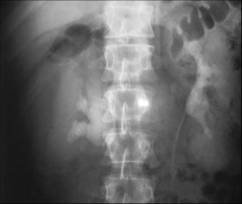

Subcapsular collection